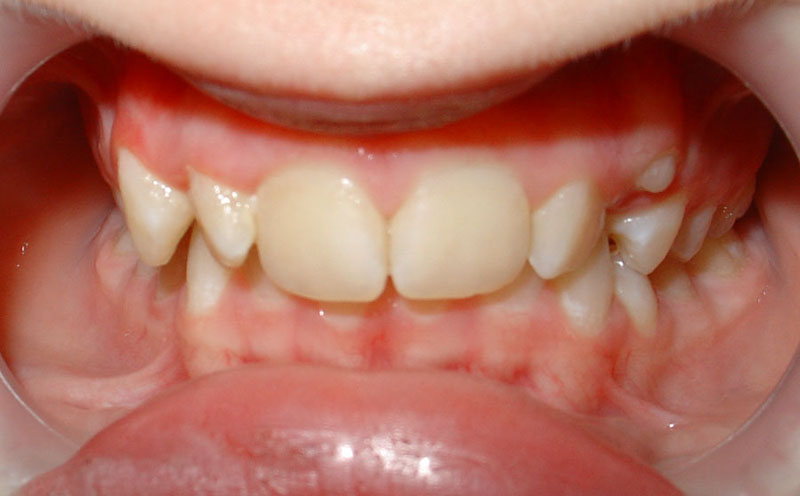

Начну с самого простого. Мальчик, 6 лет. Носил съемную плстинку 4 мес. В таком возрасте брекеты еще, как правило, не используют.